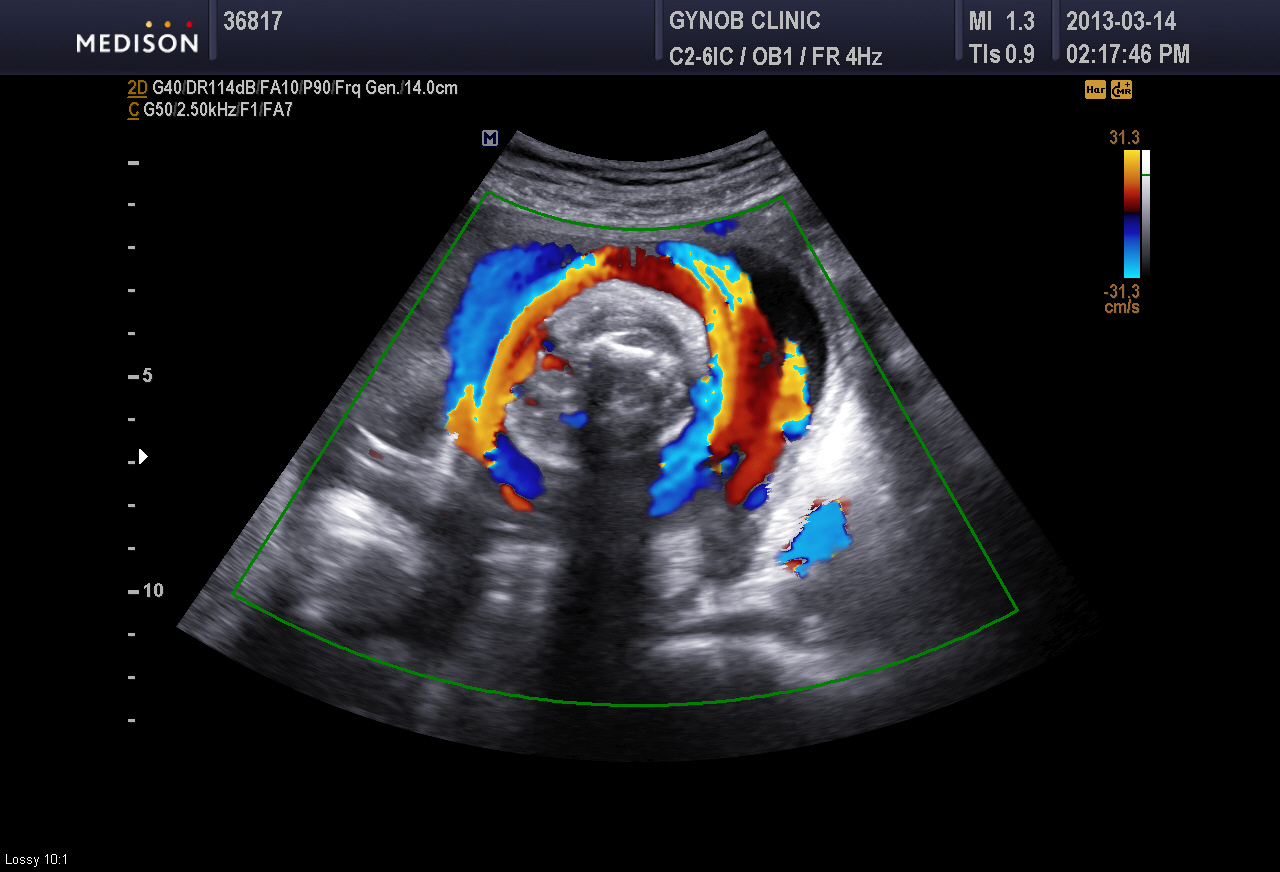

경부 제대륜의 산전 진단은 10여년전 일반 초음파만 있을 때는 진단율이 20% 수준에 머물렀지만 컬러 도플러 초음파라고 하여 탯줄의 혈액 흐름을 컬러로 살펴 볼 수 있게 되면서 진단율이  90% 수준으로 올라갔다는 연세대 산부인과 교수팀의 보고에서도 알 수 있듯이 요즘은 초음파를 이용하여 진단이 수월한 편입니다.

아래 사진은 저희 병원에서 찍은 컬러 도플러 초음파 사진으로 빨갛고 파랗게 보이는 부분이 탯줄이고 가운데 검게 둥그런 부분이 태아의 목을 수평으로 본 모습으로 1회의 경부 제대륜이 있는 모습입니다.